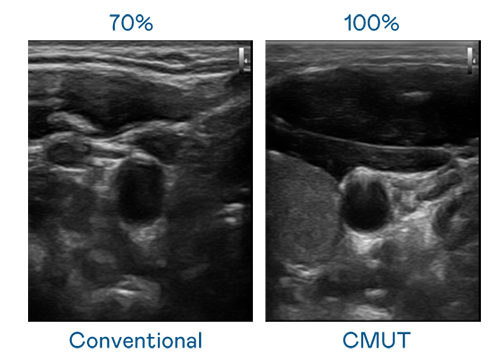

CMUT 技术是一种用电容式微机电元件来产生超音波讯号的技术。与传统 PZT 压电式技术相比,CMUT 频宽增加 30%,更宽频的超音波讯号让影像解析度大幅提升,是实现高影像品质医疗超音波扫描、促进精准医疗发展的关键技术。

超音波影像的解析度高低,首先取决于探头能发出的讯号频宽。z6人生就是博 CMUT 可提供高清晰的超音波讯号,提供高频宽、高灵敏度、影像纹理细节更高的超音波影像,协助医护人员缩短影像判读时间及利用精准的医疗影像进行诊断。